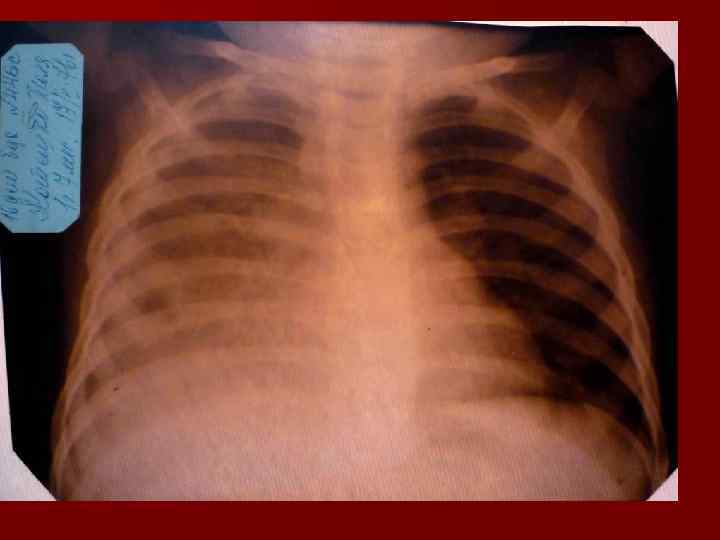

Долевая пневмония характеризуется лобарным пневмоническим инфильтратом. Крупозная ( пневмококковая) пневмония диагностируется прежде всего по клиническим данным. Крупозная пневмония сохраняет свою типичную картину пневмококковой пневмонии: острое начало с характерными клиническими данными, циклическое течение, несклонность к деструкции, гомогенной и лобарной инфильтративной тенью при рентгенологическом исследовании. Вместе с тем, широкое использование антибиотиков способствовало значительному снижению числа крупозных пневмоний у детей. Интерстициальная – редкая форма пневмоний, при которой оказывается поражен прежде всего интерстиций. Как правило, интерстициальная пневмония обусловлена вирусами, пневмоцистами, внутриклеточными микроорганизмами и грибами.

Морфологическую форму пневмонии определяют по клинико – рентгенологическим данным: выделяют очаговую, очагово – сливную, долевую ( крупозную), сегментарную и интерстициальную пневмонии. Очаговая – наиболее распространенная форма. Пневмонические очаги чаще бывают размером 1 см и более. Очагово – сливная – инфильтративные изменения в нескольких сегментах или во всей доле легкого, на фоне которых могут быть видны более плотные участки инфильтрации и/или полости деструкции. Сегментарная – в процесс вовлекается весь сегмент, который, как правило, находится в состоянии гиповентиляции, ателектаза. Морфологическая картина воспаления при очаговых и сегментарных пневмониях связана с первичным инфекционным воспалением в бронхах, что дает основание отнести эти варианты поражения легочной ткани к бронхопневмониям, нередко сопровождающихся бронхообструктивным или бронхообтурационным синдромами. В настоящее время данный тип пневмоний у детей встречается наиболее часто.